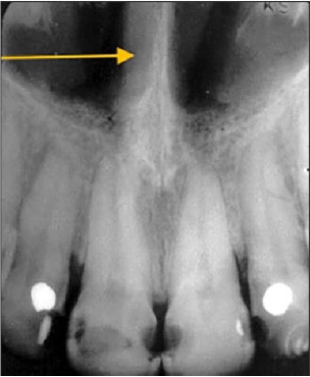

28. What is showing by arrow?